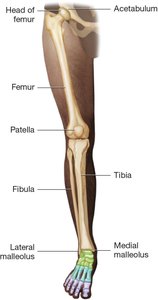

Leg, Ankle, and Foot

The femur joins the tibia to support body weight. The fibula is the smaller bone of the lower leg. The patella protects the knee joint. The tarsal bones in the ankle connect to the metatarsal bones in the foot, and each toe contains three phalanges (except the great toe, which has two).

Bones of the lower extremity including femur, tibia, fibula, patella, and foot bones Bones of the foot including tarsals, metatarsals, and phalanges